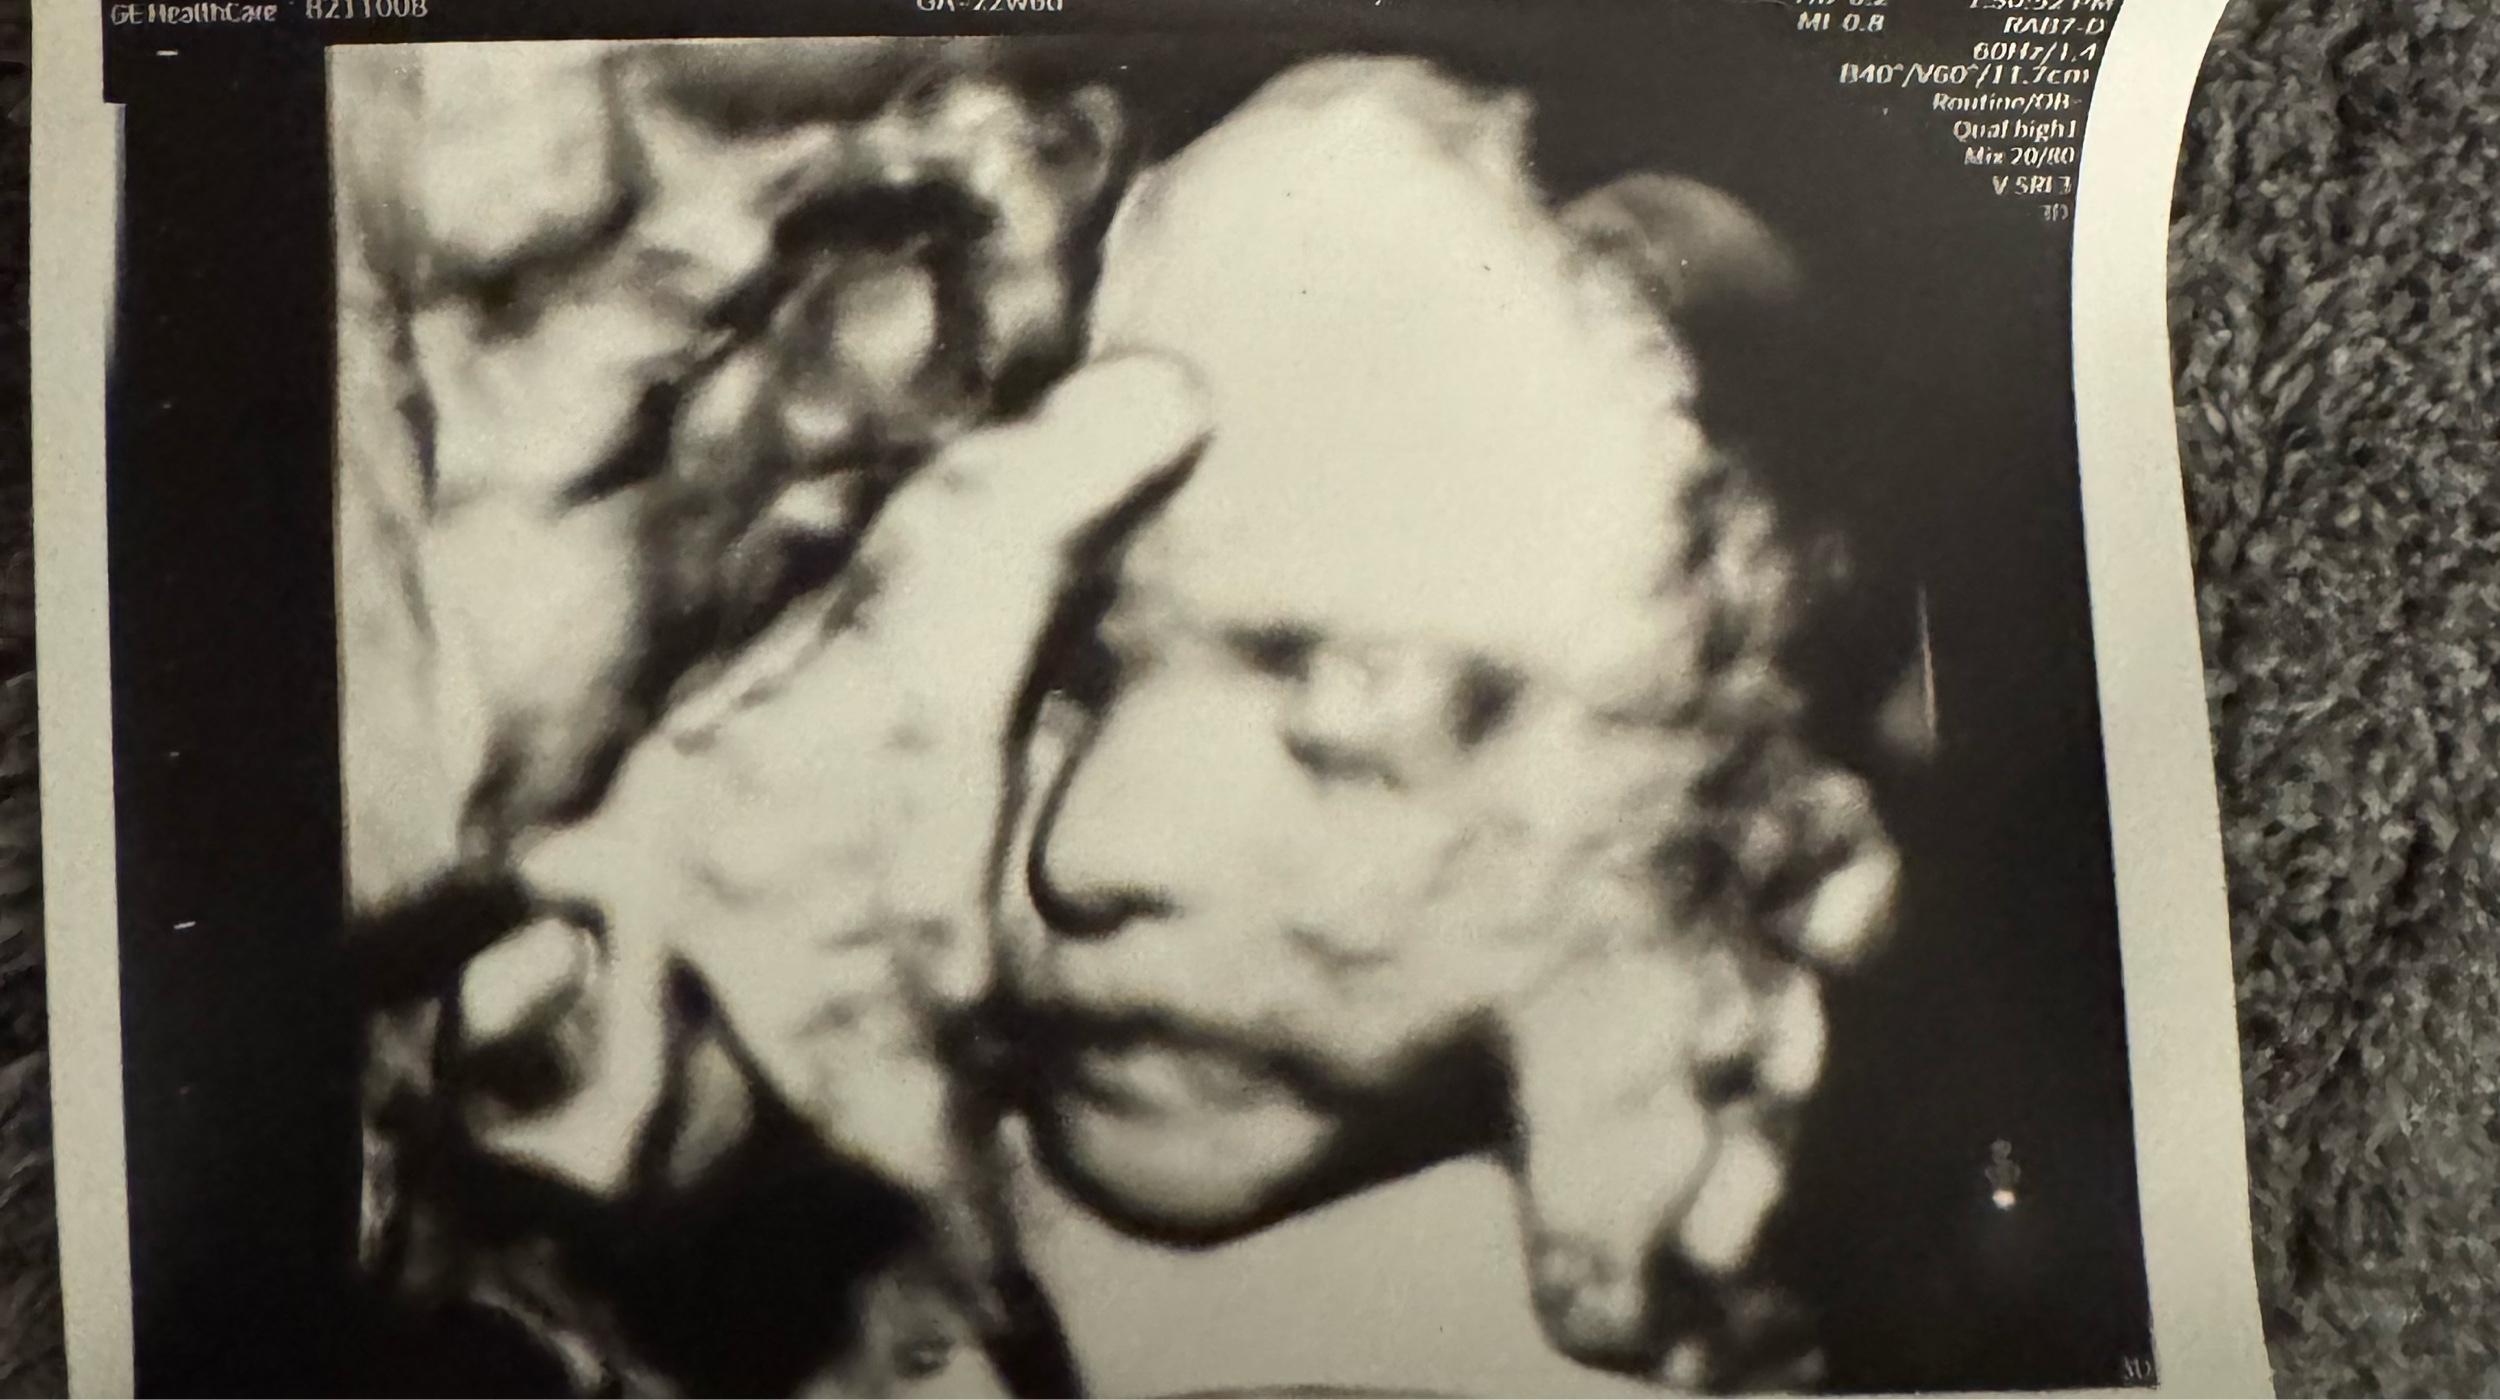

Arrival date December 11, 2025

Dear Family & Friends, Thank you so much for visiting our registry page! Ray and I could not be more thrilled and excited to become parents, and cannot wait to meet our baby girl! Thank you for all of your love and support!